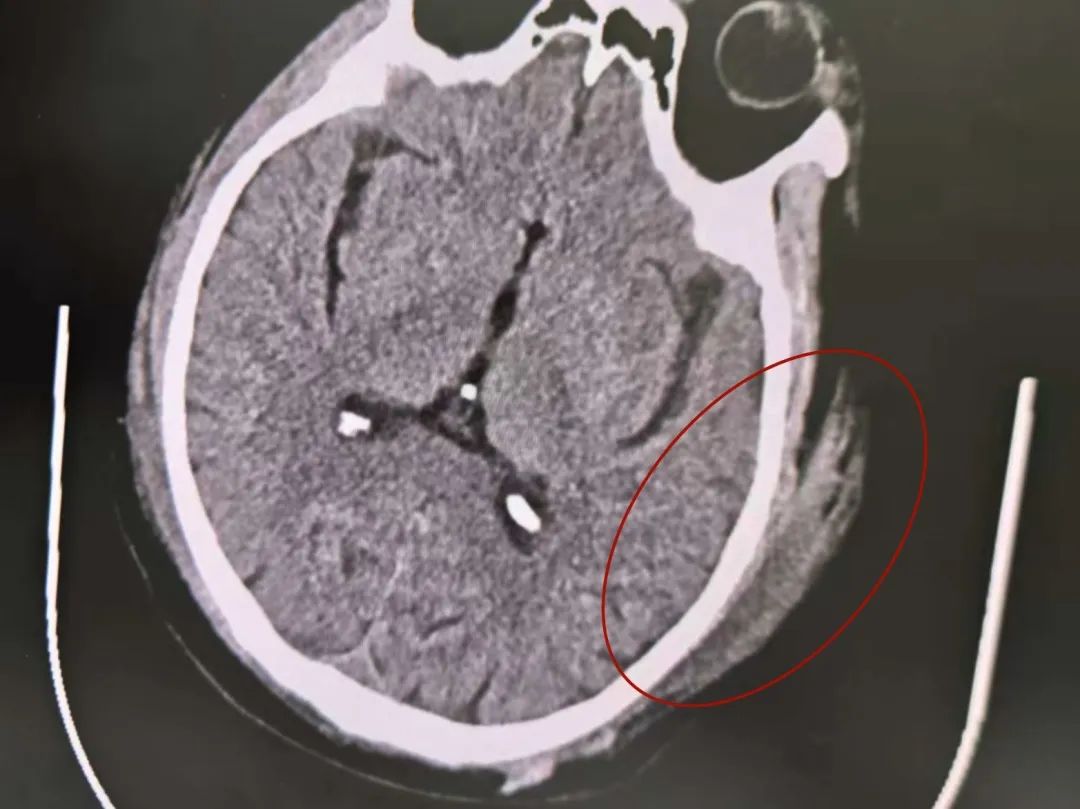

头部血肿

系统检查提示:罗叔目前存在车祸后多发伤,头部、胸部、腹部等存在多处外伤,颅脑的挫裂伤,右侧颌面部撕裂伤,右肘关节皮肤裂伤等全身多处皮肤擦伤。外表的伤口已经足够狰狞,而在罗叔的身体内部存在更严重的情况:闭合性颅脑损伤、呼吸衰竭、右侧6根肋骨骨折伴血气胸和皮下气肿、代谢性酸中毒、呼吸性碱中毒,还有肝、肺挫伤等脏器损伤。